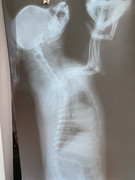

Коллапс трахеи форум